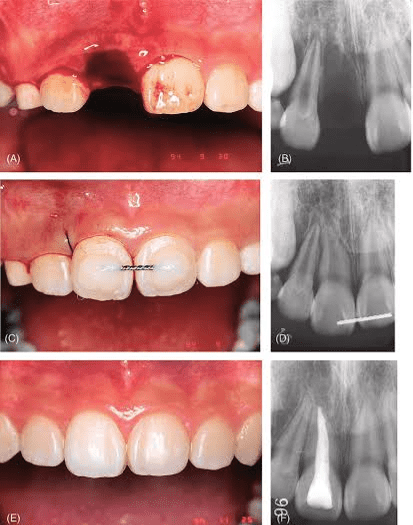

Conservative Dentistry and Endodontics is the branch of dentistry which deals with the treatment of caries , malformed, discolored , unesthetic, or fractured teeth, pulpal and periapical diseases and dental pain management. Our vision is to create an environment conductive for enhancement of restorative and endodontic skills.The department has set up its own high standard in patient care, education and research.

• More than 1000 Root Canal Treatments by each Post Graduate Student under Rubber Dam Isolation.

• Apexification & Apexogenesis

• Retreatment Procedures

• Fibre Post –Core

• Hemisection, radisection & bicuspidization

• Endodontic Revascularisation